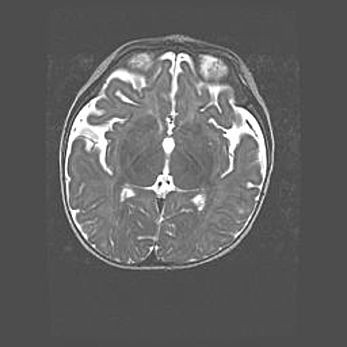

Мальформация Денди-Уокера. Киста задней черепной ямки.

Агенезия мозолистого тела.

Возраст: 2,5 месяца

Вес: 2420 г

Пол: женский

Окружность головы: 37 см

Срок гестации: 32 недели

Мальформация Денди—Уокера — редкий вид патологии ЦНС, представляющий собой врожденный порок развития каудального отдела ствола и червя мозжечка, ведущий к неполному раскрытию срединной (Мажанди) и латеральных (Лушка) апертур IV желудочка мозга. Для этогно синдрома характерна триада симптомов: гипотрофия червя мозжечка и/или полушарий мозжечка, кисты задней черепной ямки, гидроцефалия различной степени. В 70% случаев порок сочетается и с другими аномалиями головного мозга, в частности с агенезией мозолистого тела.